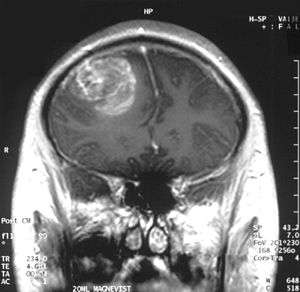

| Coronal MRI with contrast of a glioblastoma WHO grade IV in a 15-year-old male | |

When viewed with MRI, glioblastomas often appear as ring-enhancing lesions. The appearance is not specific, however, as other lesions such as abscess, metastasis, tumefactive multiple sclerosis, and other entities may have a similar appearance.[43] Definitive diagnosis of a suspected GBM on CT or MRI requires a stereotactic biopsy or a craniotomy with tumor resection and pathologic confirmation. Because the tumor grade is based upon the most malignant portion of the tumor, biopsy or subtotal tumor resection can result in undergrading of the lesion. Imaging of tumor blood flow using perfusion MRI and measuring tumor metabolite concentration with MR spectroscopy may add value to standard MRI in select cases by showing increased relative cerebral blood volume and increased choline peak respectively, but pathology remains the gold standard for diagnosis and molecular characterization.